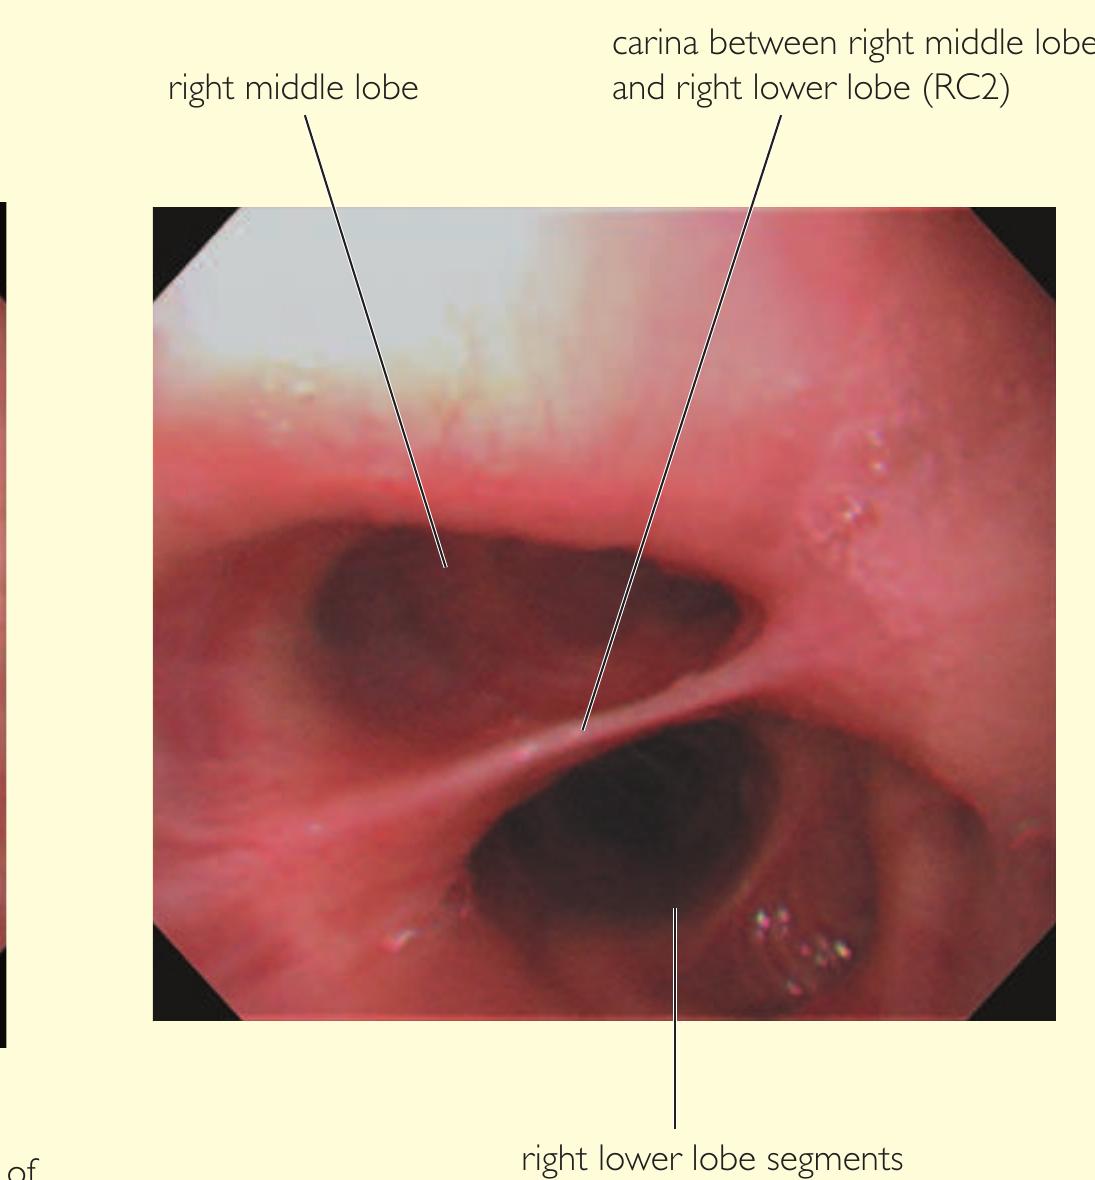

- Our approach, for example, for the right lower lobe is to treat RB10 (right posterior basal bronchus) first, using the BF260 bronchoscope (external diameter 4.3 mm) so that the distal subsegments can be assessed.